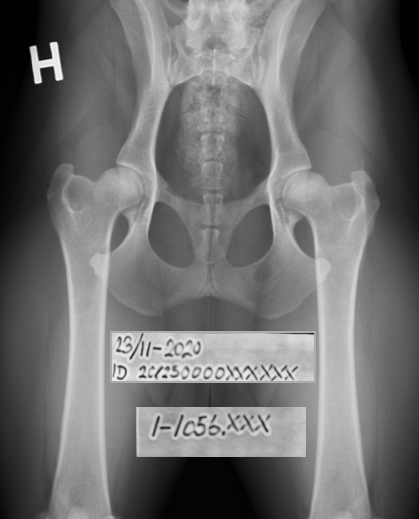

DKK er blevet pålagt at følge FCI's regler for mærkning af røntgenbilleder. Det betyder, at røntgenoptagelser af DKK-hunde, der indsendes til screening for HD, AD og OCD, skal være permanent mærkede med mærkningstape, der angiver dato for optagelse, ID på hunden, samt sagsnummer. Mærkningen skal altså være indfotograferet på selve optagelsen. Billederne nedenfor viser, hvordan mærkningen skal være udformet og placeret. Ordningen er indført af FCI for at forhindre snyd, da det er påvist at man – også i DICOM – kan ændre på de data, der er tastet ind, så de samme billeder kan sendes ind med forskellige identiteter. Naturligvis er det umuligt at sikre sig 100% imod snyd, men det er altså bagrunden for FCI’s krav.